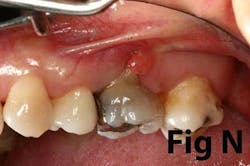

There is an abundance of literature showing increased gingival inflammation around natural dentition (exacerbated when a fixed restoration is present) when there is less than 2 mm AG. (Figs. 8, 9: post grafting) There is an abundance of literature showing increased incidence of peri-implant mucositis when there is inadequate attached tissue — a weaker connective tissue adhesion and lack of Sharpey’s fibers make the peri-implant tissue even more susceptible to bacterial challenge. (1-6, 8, 10) And as periodontitis is always preceded by gingivitis, peri-implantitis will be preceded by peri-implant mucositis. If we can decrease the incidence of peri-implant mucositis by providing a better and more resilient tissue phenotype, we can lower the incidence of peri-implantitis.The FGG procedure is indicated in cases of implant therapy where this is less than 2 mm of attached tissue present. Sometimes, a FGG is preferred over CTG because: (1) the FGG results in greater gain of attached tissue, (2) the FGG alleviates frenum/muscular pull whereas the connective tissue may increase muscular tension after the flap is coronally advanced, and (3) creeping attachment is often a positive byproduct of the FGG procedure.

Refer to Case Nos. 1 & 2.

Case No. 1